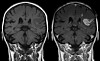

Trombolytisk behandling innen 4,5 timer Kritisk tid for trombolytisk behandling ved hjerneinfarkt er justert: Behandling har god effekt opptil 4,5 timer etter hjerneinfarktet.

Hjerneslag og behandling Trombolytisk behandling kan kurere skadene ved et hjerneslag. Likevel er det mindre enn to prosent av pasientene som får denne behandlingen.